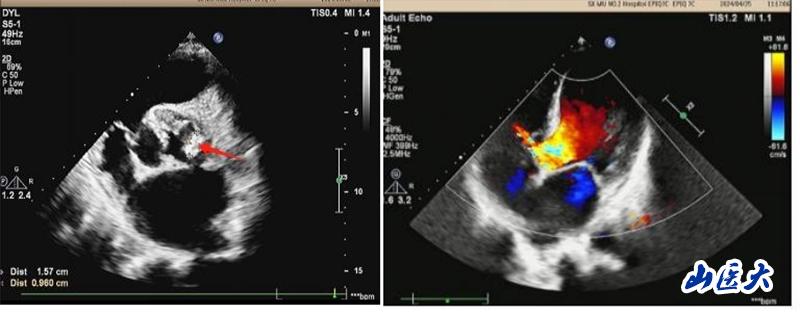

患者系一名中年男性,20余年前在當(dāng)?shù)蒯t(yī)院體檢發(fā)現(xiàn)心臟雜音,但未進(jìn)一步診治。2024年3月初開(kāi)始間斷出現(xiàn)發(fā)熱、胸悶、氣短,體溫高達(dá)38.5℃,伴咳嗽、咳白色痰液,不能平臥休息,伴雙下肢水腫、食欲不振,就診于我校第二醫(yī)院心血管內(nèi)科。行心臟彩超等輔助檢查后診斷為:感染型心內(nèi)膜炎、主動(dòng)脈瓣贅生物,主動(dòng)脈瓣二瓣化畸形伴重度關(guān)閉不全,二尖瓣中度關(guān)閉不全,室間隔缺損,肺動(dòng)脈高壓。布氏桿菌感染進(jìn)一步加重了心功能衰竭。心血管內(nèi)科周榮副主任醫(yī)師為其制定了精細(xì)的治療方案,給予抗感染、利尿等多種措施治療后,患者上述癥狀稍緩解,但須手術(shù)治療方能徹底痊愈。

患者轉(zhuǎn)入心胸外科后,馬捷主任醫(yī)師根據(jù)患者病史長(zhǎng)、心功能差、合并多個(gè)瓣膜病變和長(zhǎng)期心內(nèi)分流畸形的病情特點(diǎn),為其制定了個(gè)體化的診療方案,積極調(diào)整患者心、肺功能,改善營(yíng)養(yǎng)狀態(tài),創(chuàng)造手術(shù)機(jī)會(huì)。5月14日,馬捷主任醫(yī)師、李強(qiáng)副教授團(tuán)隊(duì)在麻醉科、手術(shù)室等多學(xué)科的密切配合下,為患者成功實(shí)施了心臟手術(shù):切除病變的主動(dòng)脈瓣、植入主動(dòng)脈機(jī)械瓣、行室間隔缺損修補(bǔ)術(shù)以及二尖瓣成形術(shù)。經(jīng)過(guò)醫(yī)護(hù)團(tuán)隊(duì)的不懈努力,以及患者和家屬的積極配合,患者經(jīng)受住了復(fù)雜心臟手術(shù)的風(fēng)險(xiǎn),終獲新生,體力、睡眠和食欲都恢復(fù)到正常人的水平,心臟惡液質(zhì)得以逆轉(zhuǎn),目前即將痊愈出院。術(shù)后復(fù)查心臟超聲,各瓣膜功能恢復(fù)良好。